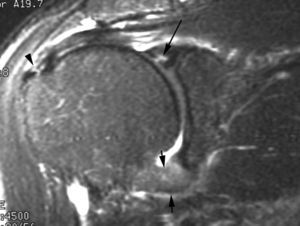

ALPSA (anterior labroliamentous periosteal avulsion)

Al igual que en el apartado anterior, existe también una separación de LG junto con la cápsula y el periostio, pero a diferencia de las lesiones de Bankart o Perthes, el LG se desplaza hacia dentro, por detrás del borde de la glenoides18 (fig. 12). La lesión de ALPSA puede cicatrizar por sinovialización (fig. 12), pero continúa siendo de carácter inestable.

Fig. 12.--ALPSA (anterior labroliamentous periosteal avulsion) agudo (A) y crónico (B). Nótese la separación del labio glenoideo y su desplazamiento posterior y medial por detrás del reborde glenoideo (flecha en A). En una fase crónica el labio glenoideo no se distingue como una estructura separada, sino como un engrosamiento de la unión entre el labio, la cápsula y el periostio (flecha en B).